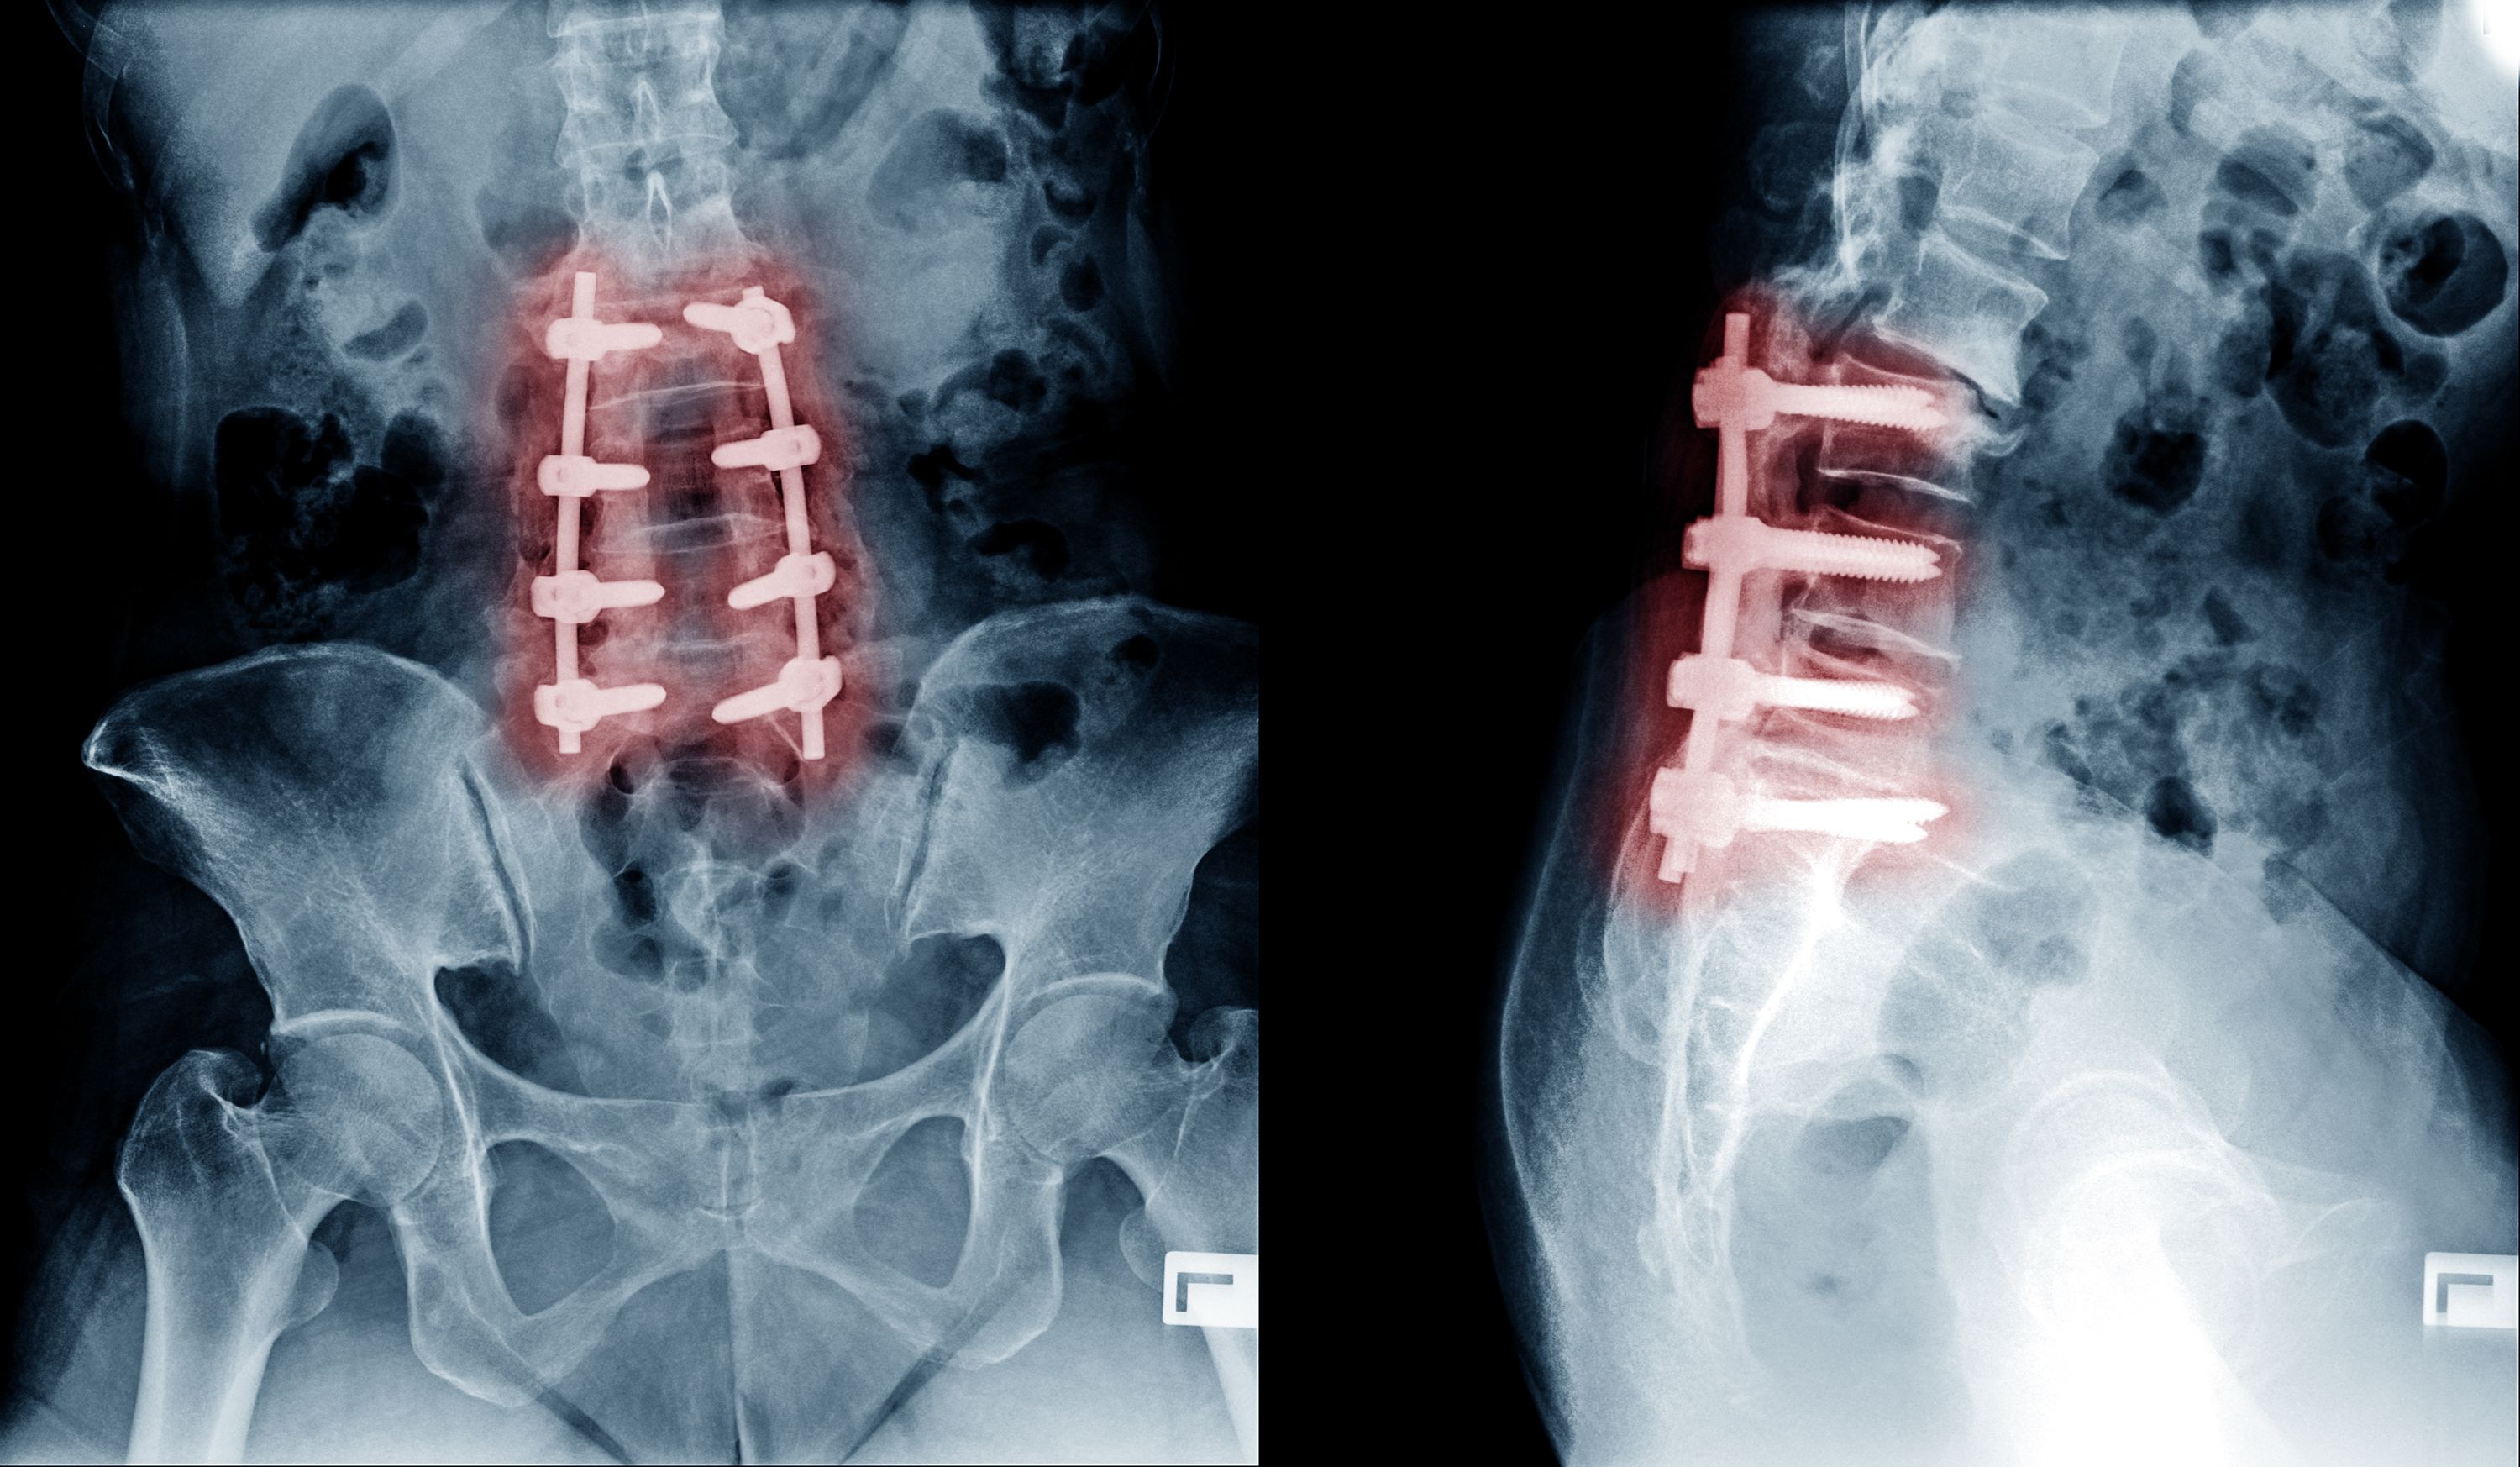

These procedures do not qualify for a guarantee because they do not cure pain and often cause more pain after surgery: